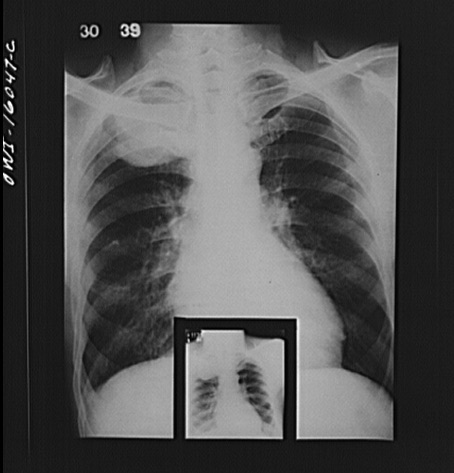

Of course it doesn’t have to be this CD-ROM way. If there ever were an irrefutable argument for the benefits of digitizing medical information, the switch from hard copy “films” to digital images would have to be right near the top. Think of how far we’ve come from the days of searching for x-ray films that, not surprisingly, would disappear in direct proportion to how interesting the case, or how sick the patient.

difficult interprectation lead to diagnosis .